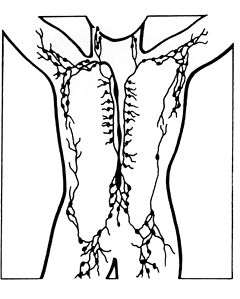

Lymphatic system

Lymphatics of the arm

Lymphatics of the axillary region